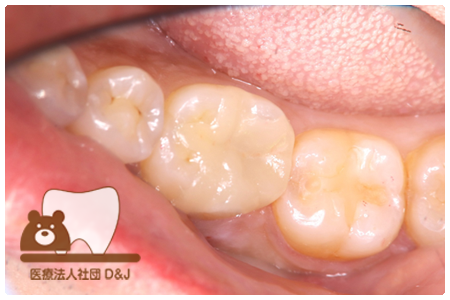

症例4フルジルコニアクラウン 左下6

治療前

治療後

37歳 男性

- 治療内容

- 以前のクラウンがセメントの劣化により外れた為その上にフルジルコニア製の被せ物を装着しました。見た目と強度を両立した自由診療の治療です。

- 治療期間

- 1カ月

- 費用

- 自費

フルジルコニアクラウン:77,000円(税込)

(R8.1月時点)

- その他の治療の費用は含まれておりません。

- リスク・副作用

- 硬い素材のため、かみ合う歯に負担がかかることがあります。将来取り外す場合に歯に負担がかかることがあります。強い力が加わると、まれに欠けたり割れたりすることがあります。